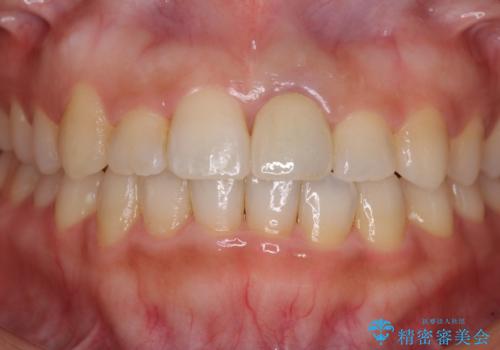

前歯のクロスバイトと変色した歯 ワイヤー矯正とセラミック治療

- 前歯のクロスバイトと神経を取り除いた後に変色してしまった前歯を気にして来院された患者様です。

ワイヤー矯正により矯正治療を行った後に、前歯の補綴治療を行うこととしました。